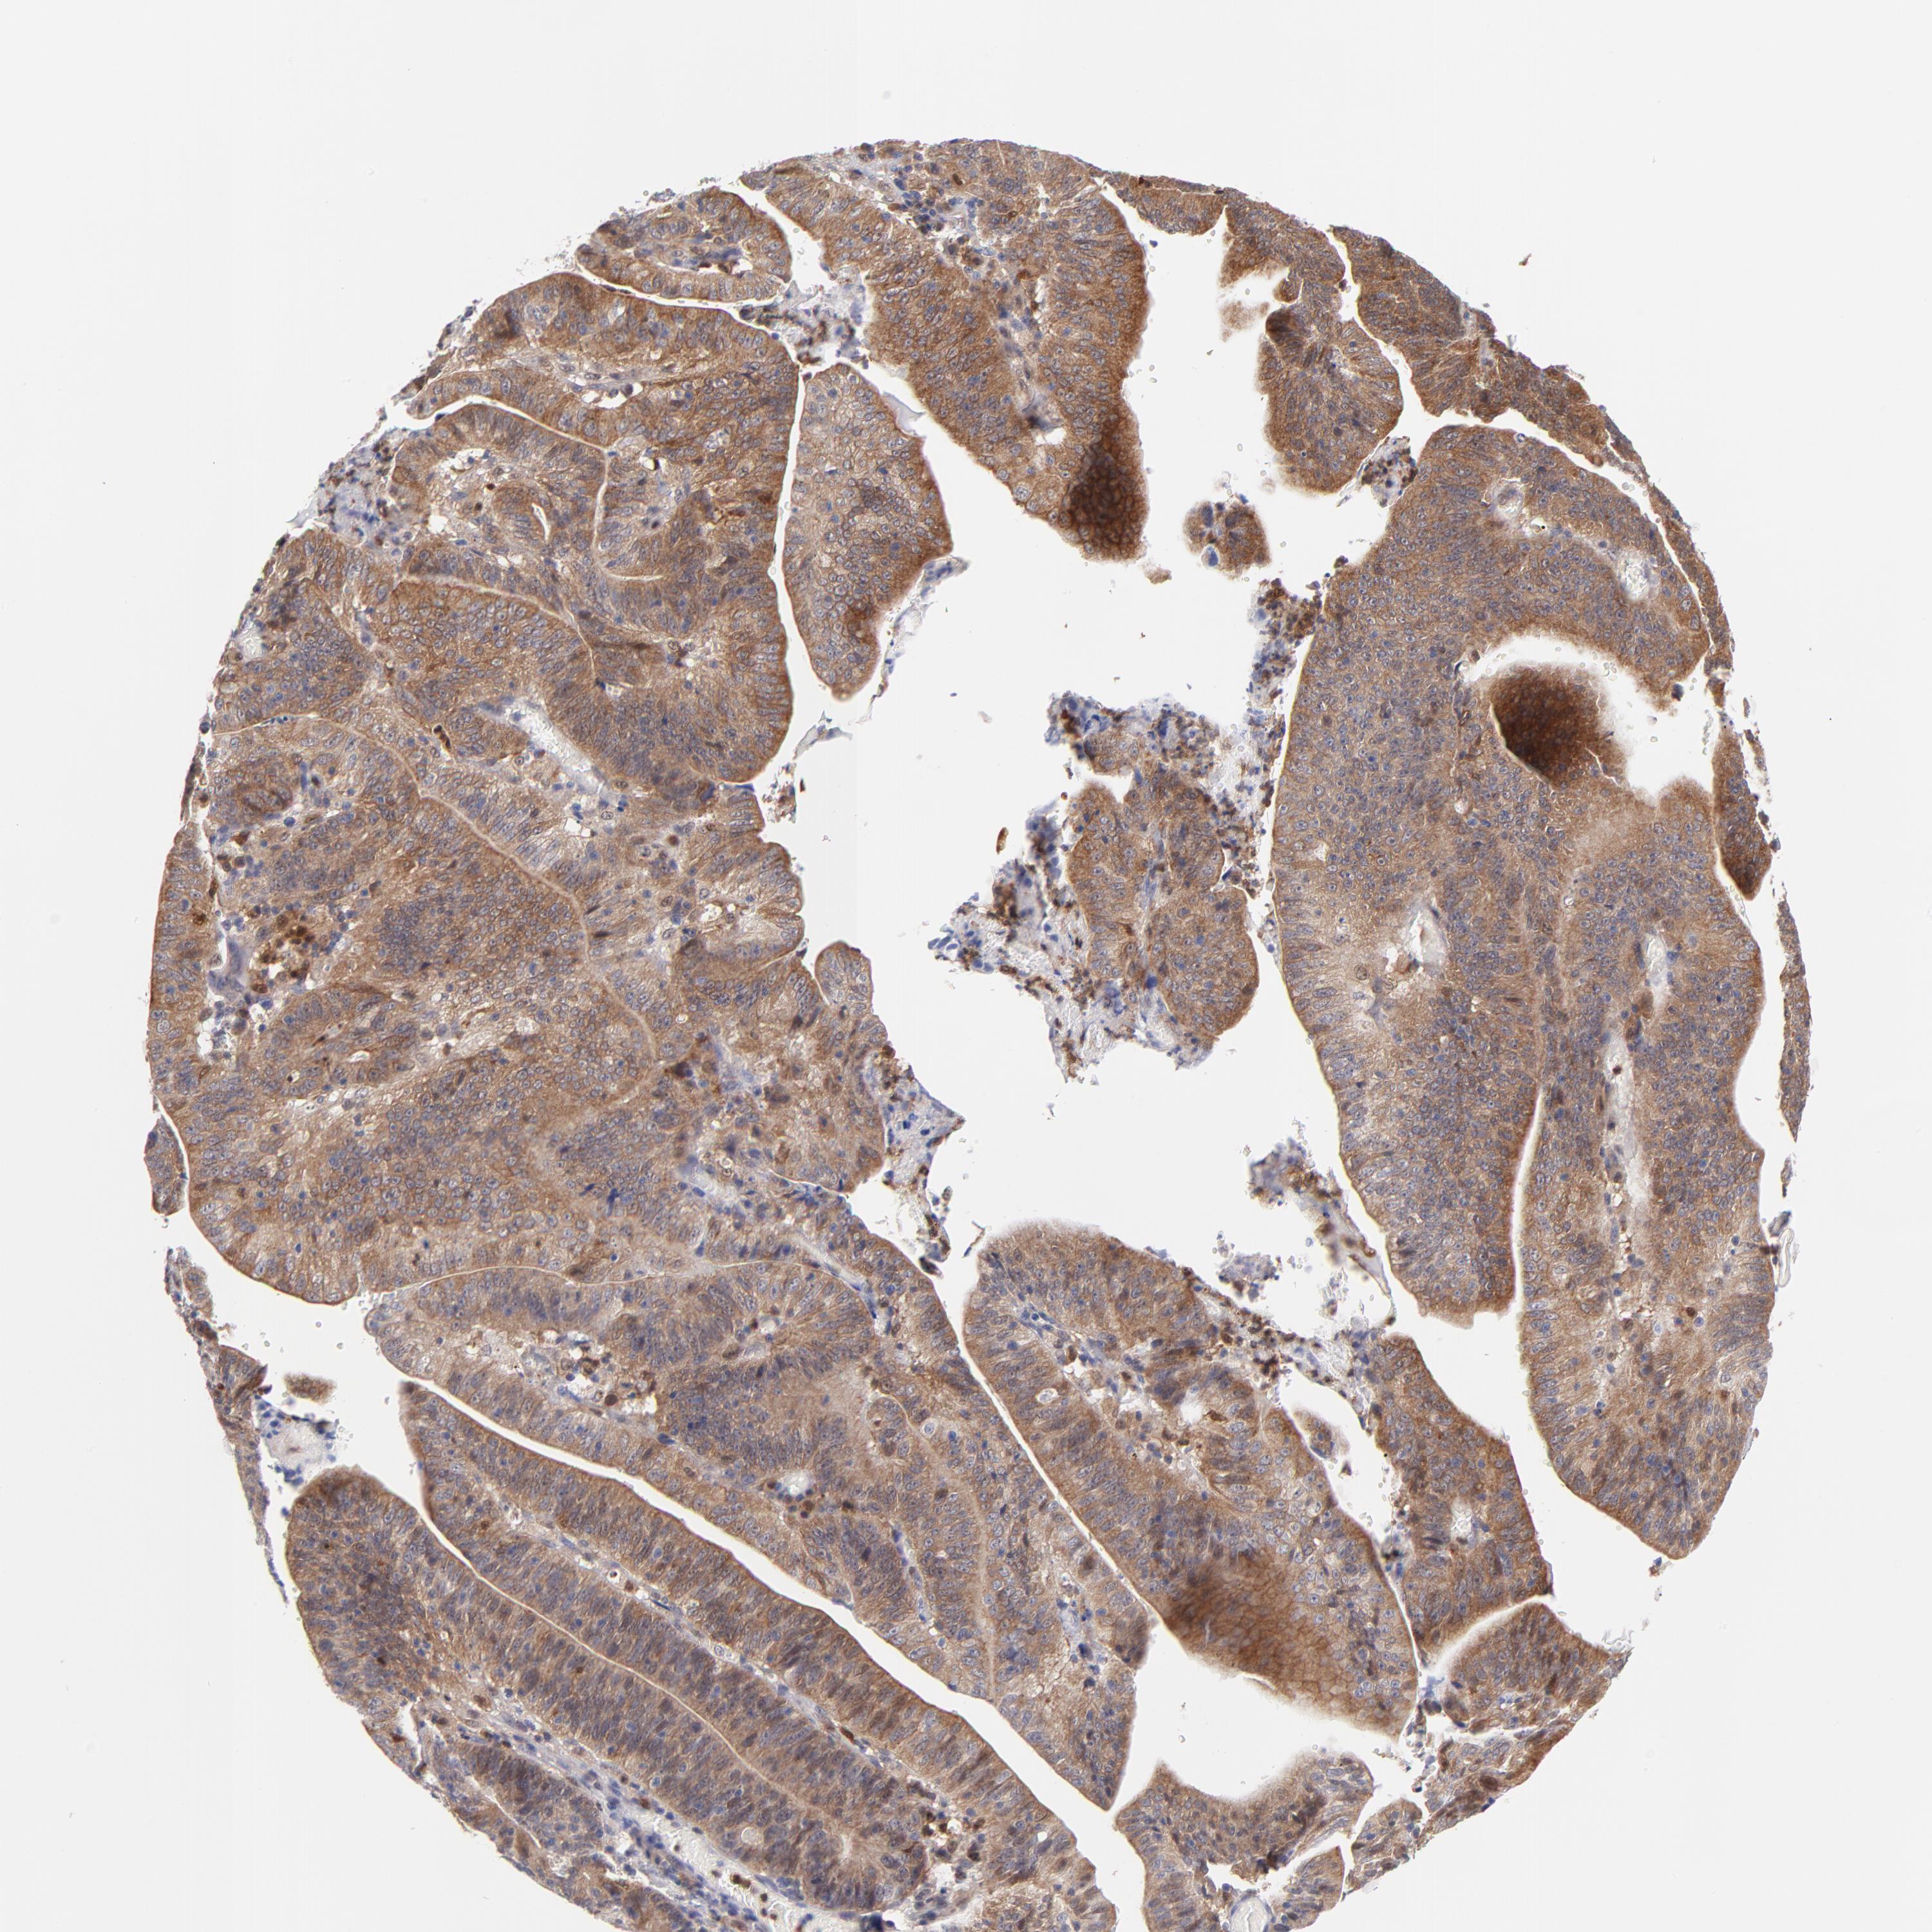

STOMACH CANCER - Protein expressioni

A mouse-over function shows sample information and annotation data. Click on an image to view it in a full screen mode. Samples can be filtered based on level of antibody staining by selecting one or several of the following categories: high, medium, low and not detected. The assay and annotation is described here.

Antibody stainingi

Antibody staining in the annotated cell types in the current human tissue is reported as not detected, low, medium, or high, based on conventional immunohistochemistry profiling in selected tissues. This score is based on the combination of the staining intensity and fraction of stained cells.

Each image is clickable and will lead to virtual microscopy that enables deeper exploration of all samples and also displays staining intensity scores, fraction scores and subcellular localization as well as patient and tissue information for each sample.

Antibody HPA000722

Antibody CAB003771

Staining

High

Medium

Low

Not detected

Intensity

Strong

Moderate

Weak

Negative

Quantity

>75%

75%-25%

<25%

None

Location

Nuclear

Cytoplasmic/membranous

Cytoplasmic/membranous,nuclear

Adenocarcinoma, NOS